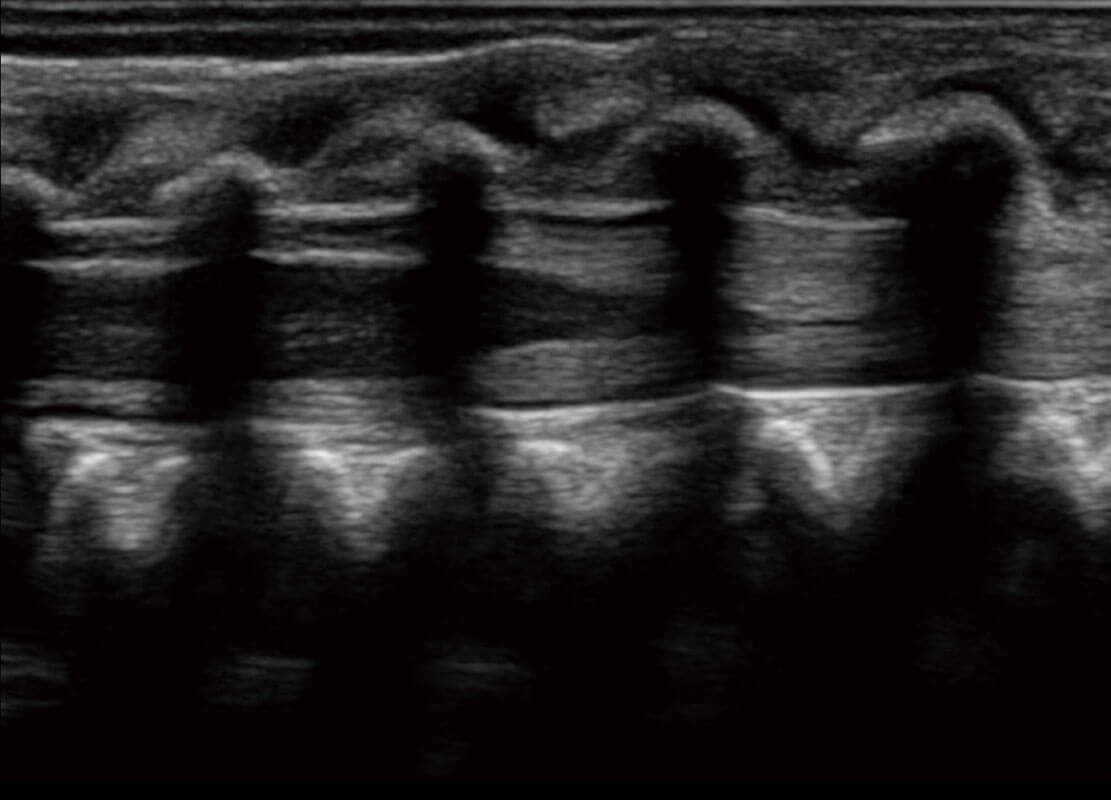

盆底超声

P60为盆底超声检查提供应用方案,多种腔内及腹部容积探头提供从二维、三维到四维的优异图像品质,实时快速三维容积数据获取,专业的测量工具包等人性化设计,为超声医生诊断提供有力保障。

S-Pelvic

能够简化盆底检查的操作流程,可在二维模式及三维成像模式下实现一键自动提取出标准切面、自动识别当前切面、自动测量,提升盆底检查的高效性,同时也能让青年医生快捷的获得准确的检查结果。